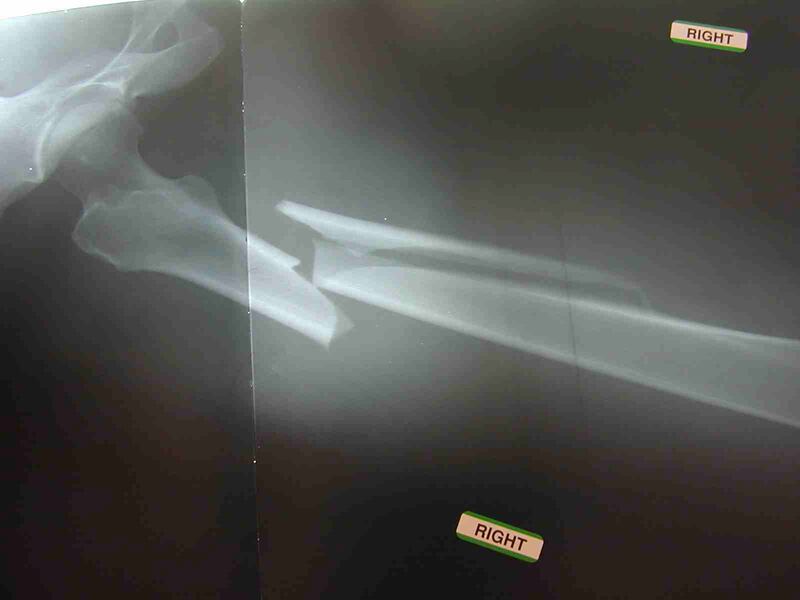

¿Y qué pasa cuándo se quiebra una cadera o un fémur? Una camilla de hospital.

Un reporte de las Fundación Internacional de la Osteoporosis (FIO) reveló que las mujeres mayores de 45 años pasan más tiempo en cama por fracturas que por males como diabetes, ataques al corazón o cáncer de mama.

En la actualidad, cerca de 200 millones de mujeres son afectadas por osteoporosis en el mundo y se estima que alrededor de una de cada tres –entre las mayores de 50 años– sufrirá una quebradura.

La osteoporosis se caracteriza por una baja densidad de la masa ósea y el deterioro generalizado del tejido de los huesos, lo cual genera la fragilidad de estos e incrementa el riesgo de fracturas.